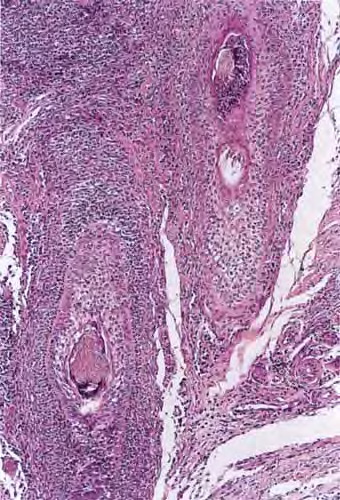

majoccchi-granuloma